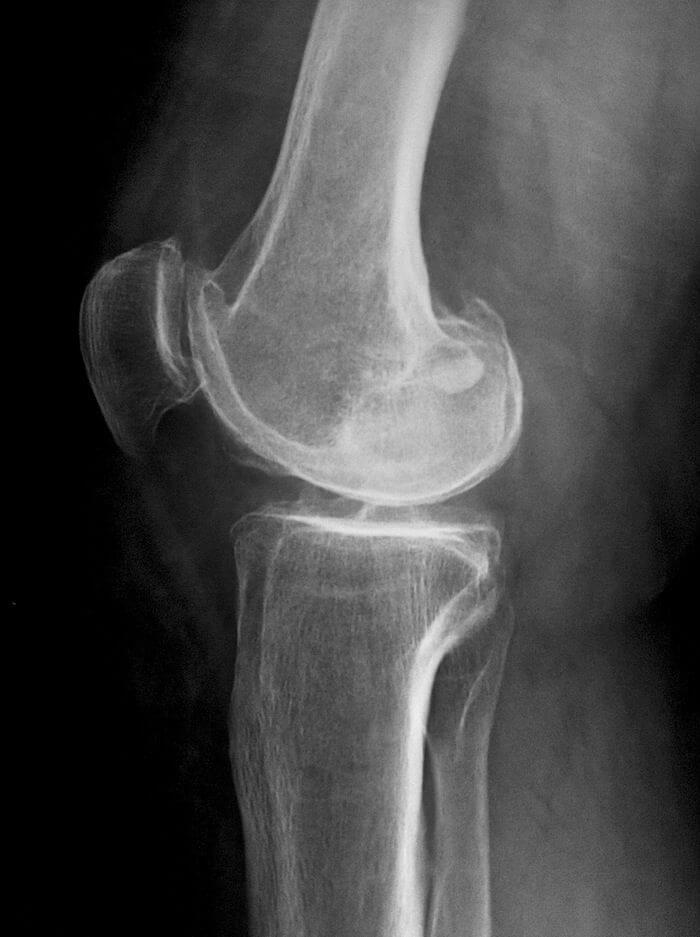

- рентгенография. На полученных изображениях хорошо заметно уменьшение высоты кости, чередование темных и светлых фрагментов в области пораженных костных тканей, изменение размеров суставной щели;